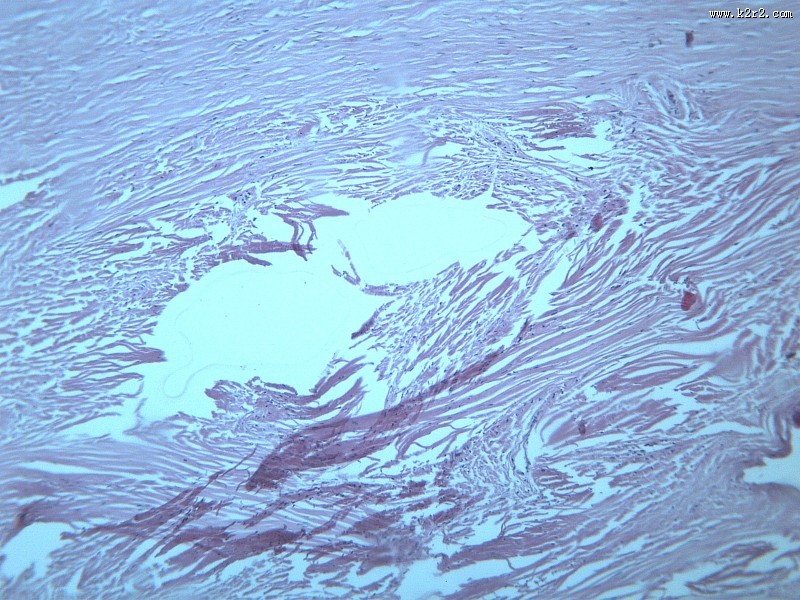

纤维瘤大全 - 第11张

纤维瘤大全

乳腺纤维腺瘤

纤维肉瘤大全

医学

显微切片

肿瘤

fibroma

纤维瘤